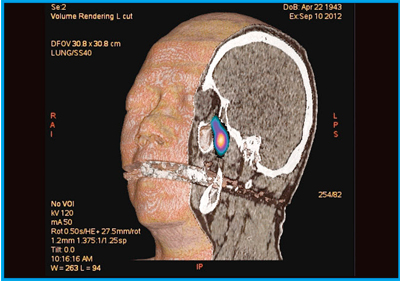

●症例4:両側眼窩下神経病変のGalium imaging

頭頸部領域は解剖学的に複雑なため,SPECT/CTが非常に有用となる。ガリウム(67Ga)シンチグラフィで,頭頸部に異常集積が認められた両側眼窩下神経病変において,生検のアプローチをしやすいように,CTの3D VR画像の断面上にSPECTの情報をカラーで表示する画像を作成した(図8)。このような画像処理が,「Advantage Workstation」(GE社製)を用いると容易に行うことができる。

図8 症例4:両側眼窩下神経病変のCT 3D VR画像とSPECTフュージョン画像